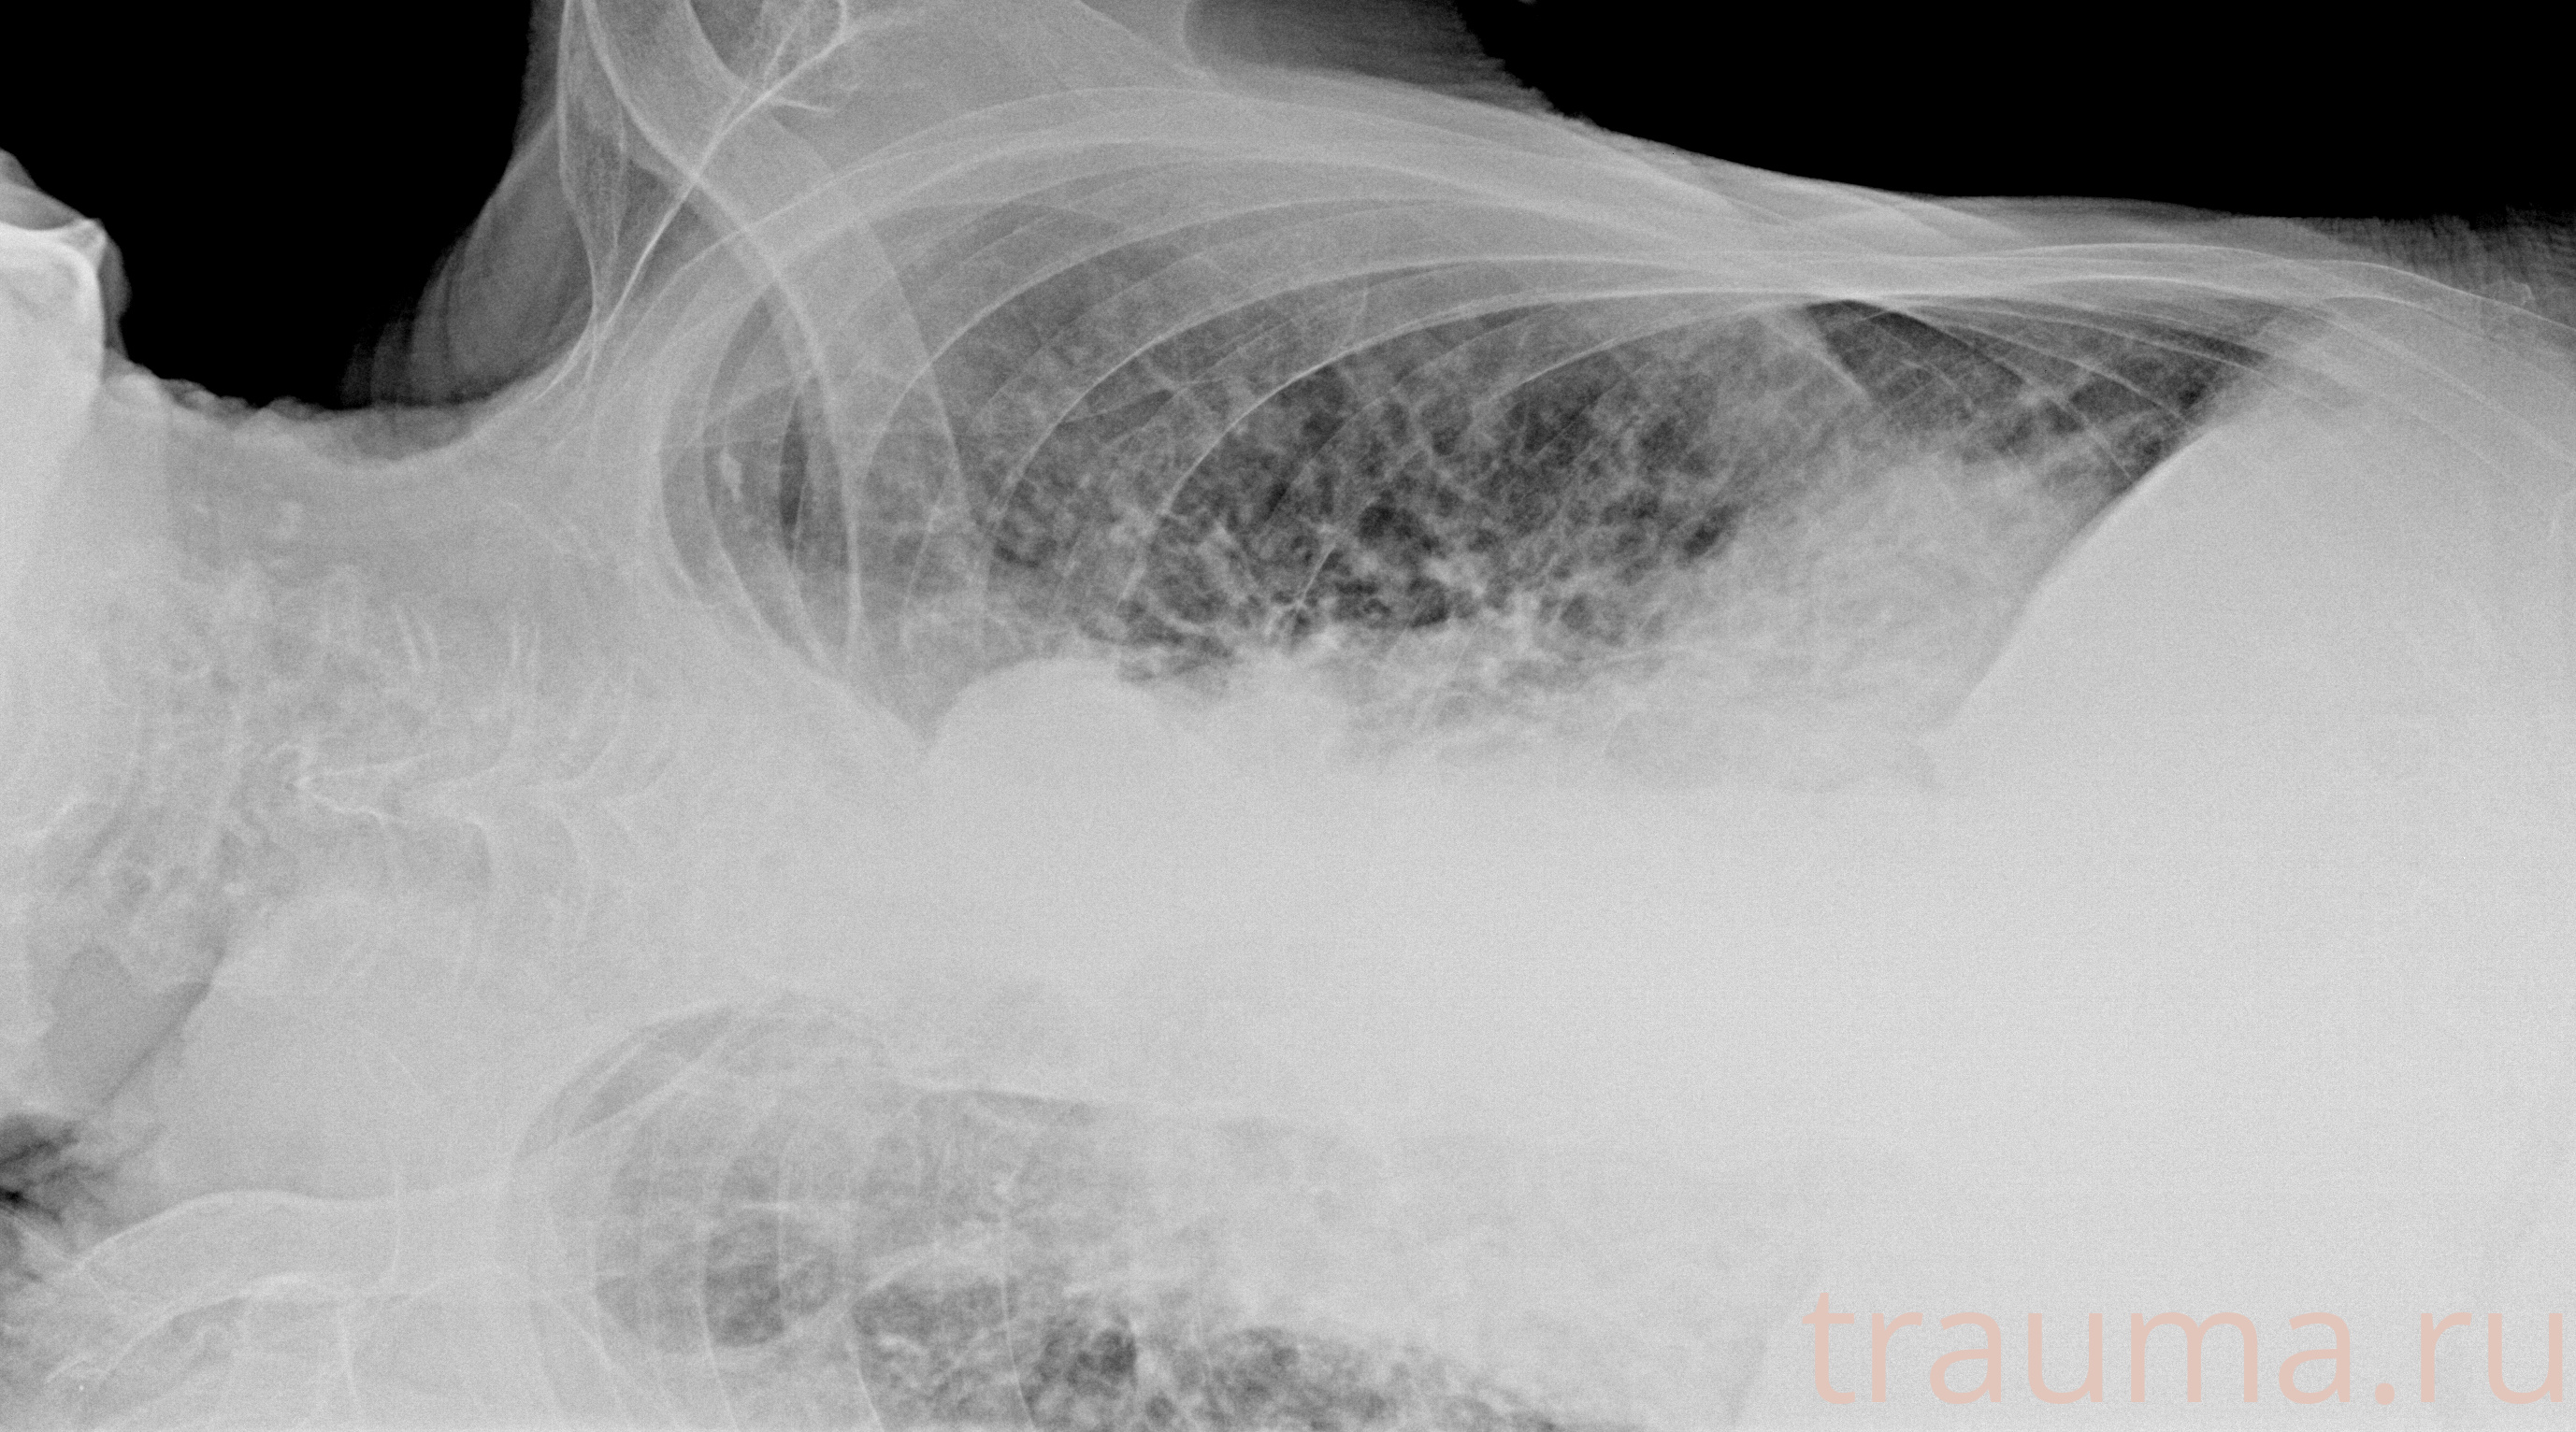

латеропозиция на правом боку